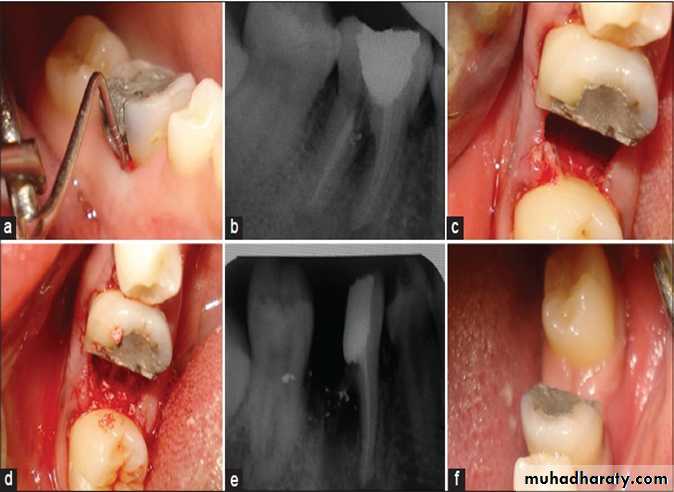

• Root separation and resection

Root seperation sectioning of root complex and maintenance of all rootsRoot resection sectioning and remove

of one or two roots in multirooted tooth

RSR used in grade II,III

Indications